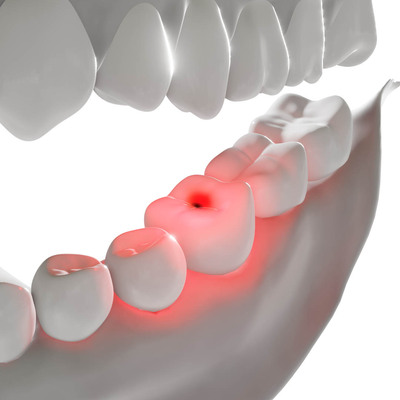

The sensation of sensitivity comes from the nerve inside the hollow center of the tooth. The two overarching causes of tooth sensitivity involve abnormalities of these important anatomical structures.

When healthy, the nerve within the hollow center of each tooth should not be able to “feel” sensations of cold, hot, sweets, etc…. However, when the healthy insulating structures are lost for any reason, the nerve can begin to feel sensations that it normally would not. Anything that weakens, cracks, or removes the enamel that insulates the nerve of the tooth can make that tooth sensitive. Also, anything leading to gum recession can make a tooth sensitive by exposing the root of the tooth. Here are a few things that can cause a loss of insulation.

It is possible to have healthy enamel and surrounding tissues while still experiencing sensitive teeth. If this is the case, tooth sensitivity likely results from a hypersensitive nerve. The nerves within each tooth can become inflamed, causing them to “overreact” to normal stimuli, such as hot and cold temperatures.